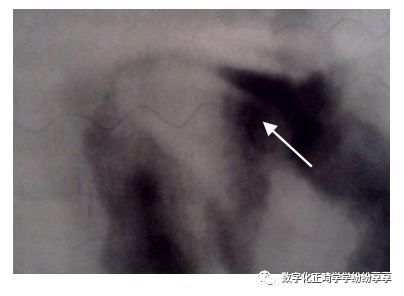

髁突硬化

曲面断层片怎么看正畸【曲面断层片(全景片)】如何解读和查看:牙周?牙体?牙髓?关节?_https://www.jmylbn.com_新闻资讯_第27张

髁突经咽侧位片示髁突前斜面密质骨不规则增生硬化

髁突前斜面模糊不清

曲面断层片怎么看正畸【曲面断层片(全景片)】如何解读和查看:牙周?牙体?牙髓?关节?_https://www.jmylbn.com_新闻资讯_第28张

髁突经咽侧位片示髁突前斜面密质骨致密影像消失,边缘模糊粗糙